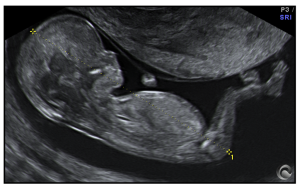

Es el método más seguro para evaluar el estado general del embarazo, cuando la gestación no supera las 13 semanas, se debe realizar por vía vaginal para poder valorar mejor.

Se introduce el transductor cubierto con un condón por la vagina y se evalúa:

- Tamaño del saco gestacional.

- Presencia de embrión.

- Si hay embarazo múltiple.

- Vitalidad del embrión.

- Distancia entre el saco gestacional y el orificio del cuello uterino.

- Si hay hematomas.

- Descartar embarazos ectópicos.

- Se calcula tiempo de gestación.